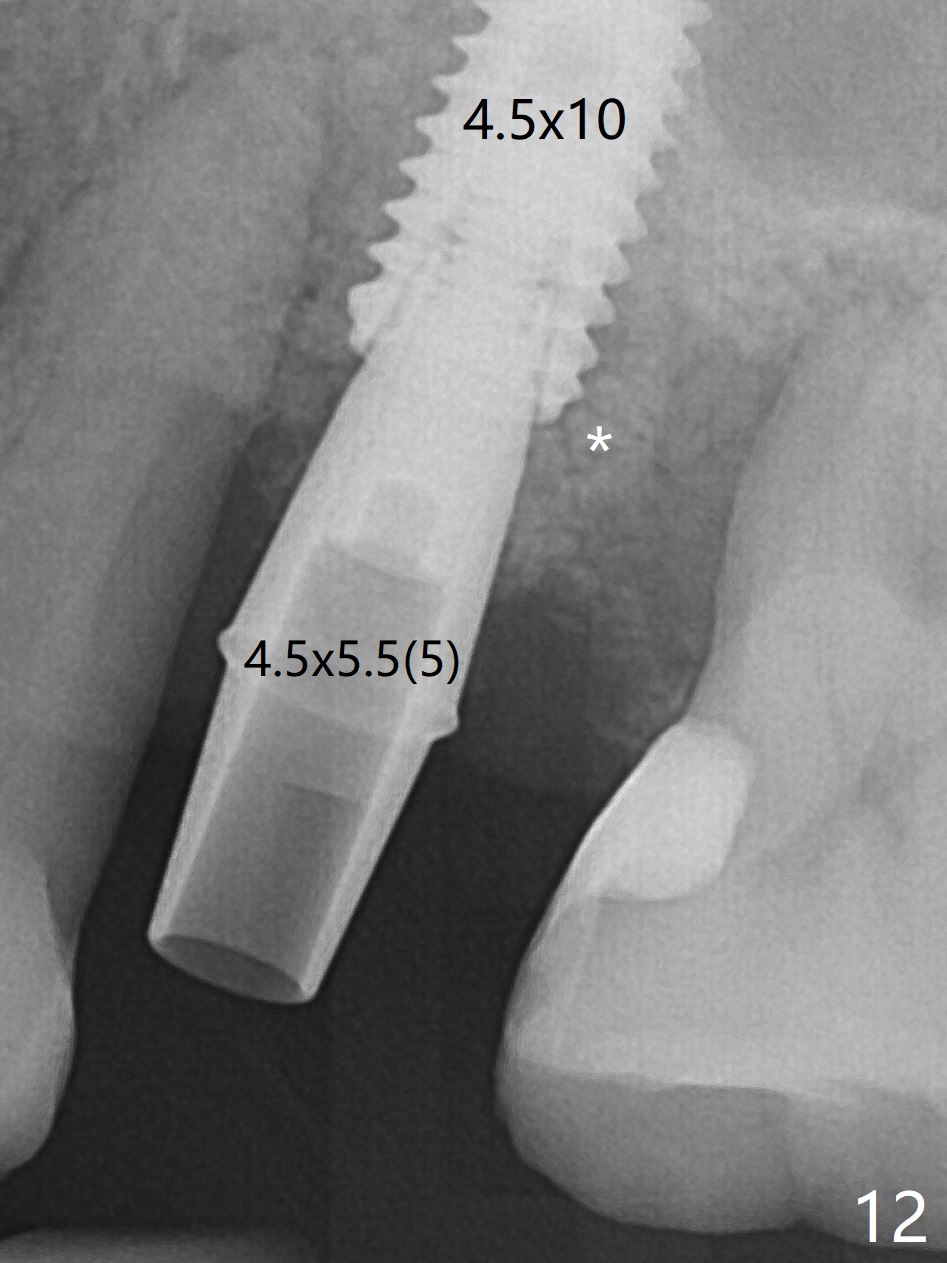

There is more bone apical to the residual root at #13 (Fig.1 red line). An immediate implant along the long axis of the root can be longer, 11.5 mm, favorable for primary stability (Fig.2 (CT taken immediately preop)). The initial trajectory is not ideal (Fig.3). When the pointed/Lindamann bur is removed (Fig.4), effort is made to move the apical end of the osteotomy distal (Fig.5 red arrow) by removing the apical bone (red dashed line). Following sequential osteotomy, a 4x10 mm dummy implant is placed with the trajectory remaining not so ideal (Fig.6,7). As the dummy implant is removed (Fig.8), a new osteotomy is established distal to the existing one (Fig.9). Subsequent drills gradually shift into the original osteotomy (Fig.10 red arrow). When the same dimension dummy implant returns, the trajectory improves with decreased stability (Fig.11). It seems reasonable to place a larger implant without further osteotomy. After placing PRF membrane and Vanilla graft for sinus lift (Fig.13 *), a 4.5x10 mm definitive implant is placed with loss of control in the trajectory (Fig.12,13).

When the initial osteotomy is off substantially (Fig.4), an osteotomy should be established de novo and as early as possible (Fig.14) so that subsequent osteotomy will not relapse to a great extent. More ideally, the initial osteotomy should be planned correctly (Fig.15,16) with sacrifice of the bone height. Nearly 1 month postop, the 4.5x5.5(5) cementation abutment is loose. When it is removed, the patient feels pain from the implant. A 5.5x6 mm healing abutment is placed instead. The implant osteointegrates with trabecular pattern in the sinus 9 months postop (Fig.20 *). The gingiva around the crown at #13 is healthy 1 year 4 months post cementation (Fig.18). Check the distal surface of #13 for bone loss if the tooth #14 is to be extracted.